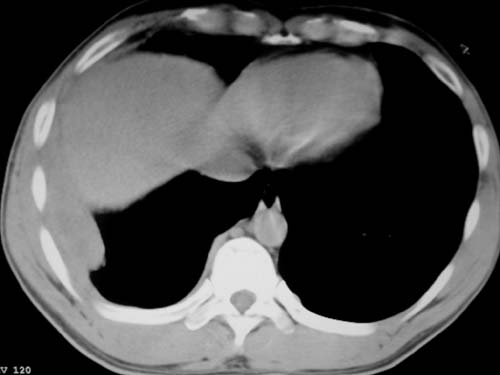

标题: CT19540: 31岁。自述结核性胸水治疗两个月后,在外院拍x线发 [打印本页]

标题: CT19540: 31岁。自述结核性胸水治疗两个月后,在外院拍x线发

右侧胸壁结节状软组织影伴相应肺叶内受侵,伴右侧胸腔积液。考虑:结核性可能大。

支持 右侧胸壁结节状软组织影伴相应肺叶内受侵,伴右侧胸腔积液。考虑:结核性可能大。

右侧胸壁结节状软组织影伴相应肺叶内受侵,伴右侧胸腔积液,结合临床,首先考虑结核。

考虑结核性胸膜炎,胸膜肥厚,不除外胸膜间皮瘤可能,建议复查。

1)考虑右侧结核性胸膜结节。2)右侧胸膜增厚+包裹性胸腔积液。